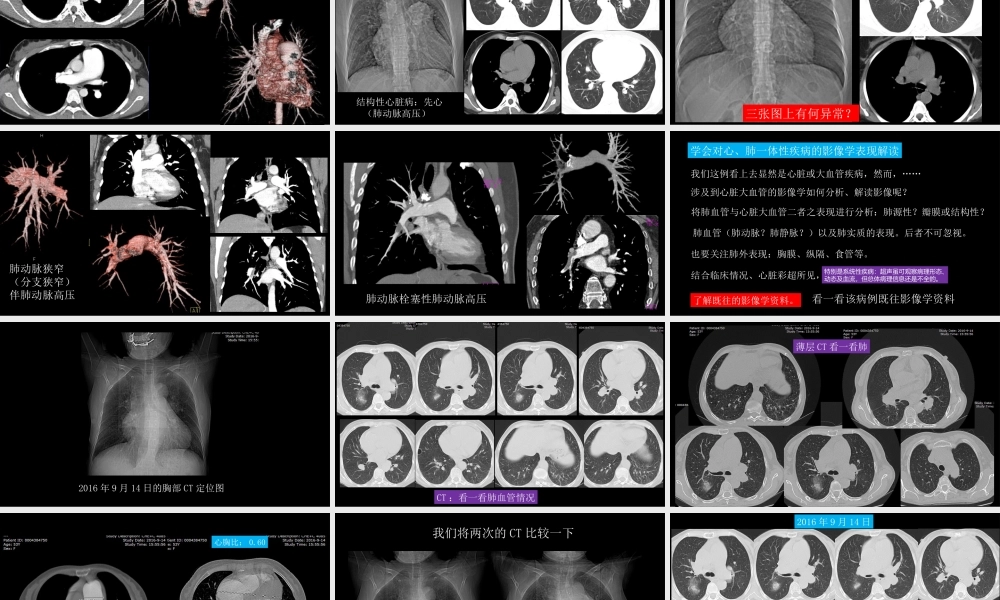

胸部影像解读:心、肺一体性疾病中国石油中心医院影像科杨景震注:内有动画设置,浏览时使用幻灯放映模式2017病例交流(1)临床近期病例女,53岁。咳嗽,气喘,不发热。白细胞及分类正常范围;持续性血氧低。2016年9月14日曾在本院CT检查,心脏增大,肺动脉增宽;心脏彩超显示三尖瓣重度返流,右心增大,以右房增大明显。2017年1月3日复查胸部CT。CT定位图2017-1-3心脏彩超提示三尖瓣大量返流、右房增大、肺动脉高压。2017-1-32017年1月3日胸部CT图薄层CT图心胸比:0.65这例看上去显然是心脏或大血管疾病,然而,……涉及到心脏大血管的影像学如何分析、解读影像呢?肺血管(肺动脉?肺静脉?)以及肺实质的表现。后者不可忽视。将肺血管与心脏大血管二者之表现进行分析:肺源性?瓣膜或结构性?也要关注肺外表现:胸膜、纵隔、食管等。结合临床情况、心脏彩超所见,注意不要被后者误导特别是系统性疾病:超声虽可观察病理形态、动态及血流,但总体病理信息还是不全的。学会对心、肺一体性疾病的影像学表现解读了解既往的影像学资料。解读心肺图像:看一看,这一例?特发性肺动脉高压结构性心脏病:先心(肺动脉高压)三张图上有何异常?肺动脉狭窄(分支狭窄)伴肺动脉高压肺动脉栓塞性肺动脉高压看一看该病例既往影像学资料我们这例看上去显然是心脏或大血管疾病,然而,……涉及到心脏大血管的影像学如何分析、解读影像呢?肺血管(肺动脉?肺静脉?)以及肺实质的表现。后者不可忽视。将肺血管与心脏大血管二者之表现进行分析:肺源性?瓣膜或结构性?也要关注肺外表现:胸膜、纵隔、食管等。结合临床情况、心脏彩超所见,注意不要被后者误导特别是系统性疾病:超声虽可观察病理形态、动态及血流,但总体病理信息还是不全的。学会对心、肺一体性疾病的影像学表现解读了解既往的影像学资料。了解既往的影像学资料。2016年9月14日的胸部CT定位图CT:看一看肺血管情况薄层CT看一看肺心胸比:0.60我们将两次的CT比较一下定位图2016-9-142017-1-32016年9月14日2017年1月3日2016年9月14日2017年1月3日2016年9月14日2017年1月3日两次的薄层CT心胸比:0.60心胸比:0.65两次的CT:肺动脉、心脏的对比1、肺动脉主干及分支扩张进行性加重,并以向外周扩展显著。2、肺组织反复出现炎性灶(磨玻璃灶为主)、马赛克征。3、心脏表现右心增大,以右心房为著。4、无肺小动脉充血征,呈“残根”现象,这与进行性(短期)肺动脉扩张及右心增大综合分析,进而排除结...